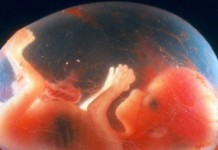

Будущий ребенок Длина его тела – около 28 см, вес – примерно 400 г. Плод похож на новорожденного в миниатюре. Губы, брови, веки уже различимы,...

Будущий ребенок На этой неделе происходит много важных изменений: малыш гримасничает, хмурит бровки, щурится и может сосать большой пальчик! Работают лицевые мышцы, изображая поочередно ту...

Будущий ребенок Длина тела малыша – уже 9,5 – 10 см от макушки до копчика. Ваш малыш размером с яблоко. Плод активно пропускает через себя...